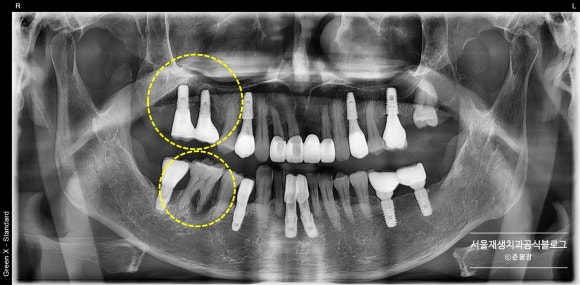

임플란트 주위의 불편감을 호소하시는 환자분의 엑스레이입니다.

어디에 어떤 문제가 있었을까요?

두 개의 노란 동그라미 중 상방에 있는 것을 먼저 보실까요?

임플란트 2개를 둘러싼 치조골(=잇몸뼈)가 완전히 녹아내렸습니다.

사실은 끝에서 두번째 임플란트의 심한 골소실에 집중하고 있었는데,

막상 구강 내에서 검사를 하니

맨 끝 임플란트 또한 심하게 흔들리고 있다는 것을 알게되었습니다.

아래의 동그라미 속에는

마찬가지로 치조골(=잇몸뼈)가 절반 이상 흡수된 자연치아가 관찰됩니다.